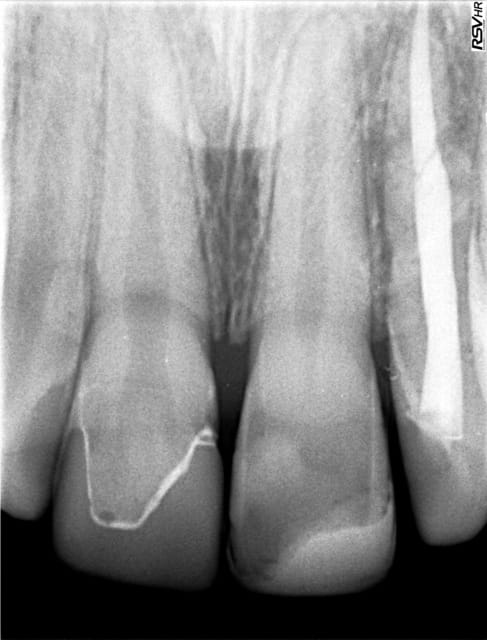

Voilà une radio (photo de la radio faite par la patient) à 6 mois.

Je vais contacter le confrère qui le suit, et aussi l'ortho qui va démarrer un trt, pour avoir plus de détails.

Dommage que l'on ait pas une belle rétro alveolaire , pour matter l espace ligamentaire .

Beaucoup de guignols vont te parler d ankylose , mais je n'en ai jamais eu lors d'une extraction reimplantation .( à ne pas confondre avec une reimplantation tardive ).

Lors d 'un controle l'autre jour , je me suis même demandé si il y avait un ligament ou plutôt une attache fibreuse .

À la radio on voit un truc épais qui ferait penser à un ligament lache alors que la tenue est beton ...même apres une force ortho avec un élastique .

Ce qui est a noter sur la rétro du confrère, c'est la différence du volume pulpaire entre 11 et 21 :

- 21 a continué son développement (volume pulpaire réduit)

- 11 : le volume pulpaire est resté identique malgré la proximité du soin ce qui suggère que le développement s'est arrêté et donc que la dent s'est nécrosée. Malheureusement tant qu'il n'y a pas de lésion visible radiologiquement, la vitalité sera compliquée à évaluée.

Je n'avais pas du tout pensé à regarder à ce niveau Art dent. Mais j'ai du mal à voir ce que tu décris par rapport à la radio de 2014.

Oui excuse moi, je n'ai pas été clair dans mon post en fait :

Sur la 11, compte tenu de la proximité pulpaire du soin initial, on aurait dû avoir soit une apposition dentinaire (principe du coiffage) soit un recul pulpaire vis à vis de "l'agression" du soin (chose que l'on remarque quotidiennement sur des soins volumineux)

Or, sur la radio de contrôle, le volume de la pulpe est resté vraiment identique, donc qu'à priori me tissus pulpaire n'a pas pu créer cette barrière de dentine en regard du soin, ce qui pourrait justement faire penser à la nécrose.